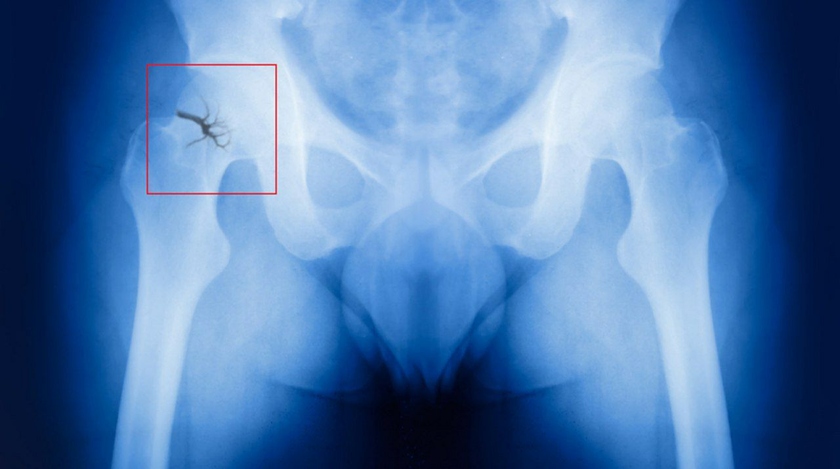

Для перелома достаточно даже падения с высоты собственного роста. Особая опасность состоит в том, что при переломе шейки бедренной кости повреждается не только кость, но и разрываются сосуды, и костный отломок (головка и часть шейки бедренной кости), лишенный кровоснабжения, может рассосаться, постепенно исчезнуть. Перелом шейки бедра в пожилом возрасте может не срастись вообще.

Рентгеновский снимок перелома шейки бедренной кости